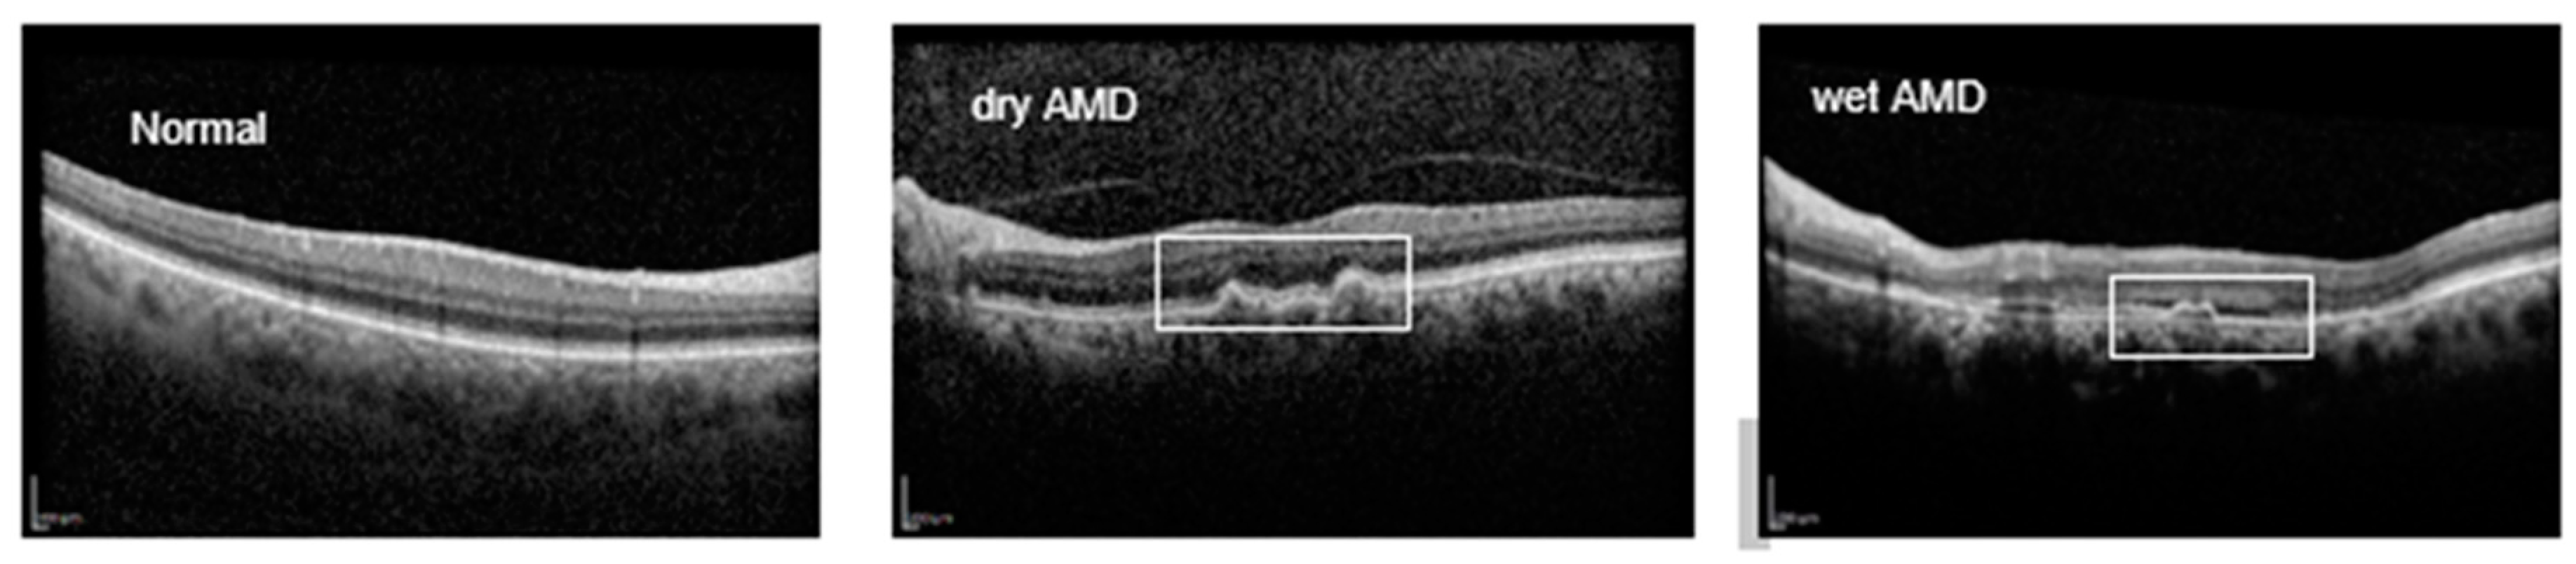

Retinal disorders are commonly diagnosed using imaging techniques such as fundus photography, fluorescein angiography, and optical coherence tomography (OCT and OCTA) [5]. OCT, a noninvasive and noncontact modality, captures high-resolution, cross-sectional images of retinal layers through low-coherence light. Its high speed, resolution, and nondestructive imaging capabilities make OCT a valuable tool for diagnosing and monitoring retinal diseases [10,11]. OCT’s utility extends beyond ophthalmology; recent studies have highlighted its relevance in detecting neurological conditions like Alzheimer’s, multiple sclerosis, and Parkinson’s disease [12,13,14]. However, OCT interpretation poses challenges. As the population ages and AMD and other chronic retinal conditions increase, the demand for OCT evaluations is straining healthcare systems. Manual OCT analysis, especially for detecting subtle or early-stage lesions, presents significant challenges, as it can be both complex and prone to misinterpretation, particularly for conditions lacking distinct visual markers in the retina. Additionally, the process can be time-consuming, with notable delays in obtaining tests, reporting results, and associated costs, which may place a burden on patients and healthcare systems. Limited data availability for rare conditions further exacerbates the difficulty in achieving accurate diagnosis and effective treatment planning. These challenges highlight the limitations of relying solely on traditional manual OCT analysis to address the growing demands of retinal care. Figure 1 provides an illustration of OCT B-scans for AMD cases

Figure 1. Sample OCT images of normal, dry AMD and wet AMD eye from the Noor Eye Hospital dataset.